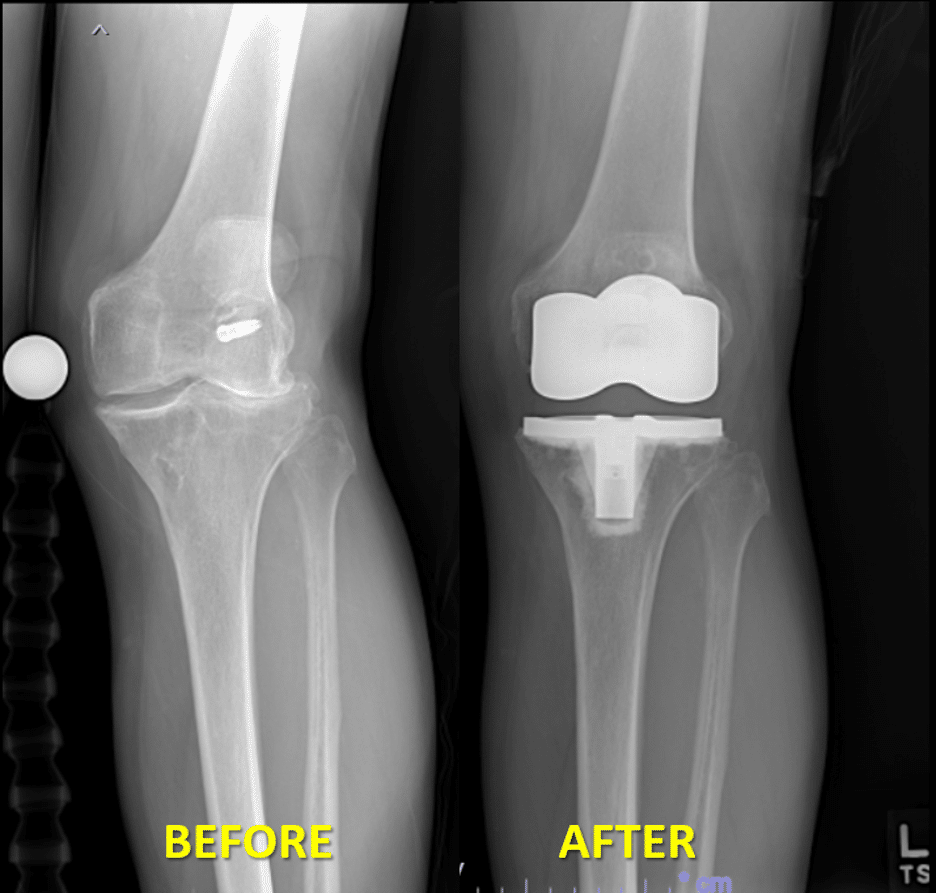

Li recommended Roy see Zayde Radwan, MD, orthopedic surgeon at UT Physicians and assistant professor in orthopedic surgery at McGovern Medical School. Radwan diagnosed Roy with tri-compartmental, post-traumatic osteoarthritis, which was likely caused by his prior knee injuries. This is different than traditional osteoarthritis which is often referred to as wear-and-tear arthritis and is the most common type of knee arthritis. Roy was bone-on-bone, especially in his lateral compartment, the outside of the knee. Radwan recommended a total knee replacement.

In January 2023, Radwan performed Roy’s knee replacement surgery. During the procedure, Radwan completed more soft tissue balancing than usual, as a result of Roy’s valgus deformity, or knock-kneed condition. The extra soft tissue balancing was required to get Roy’s knee stable for the type of activities he wanted to return to. This was a unique aspect of Roy’s case.